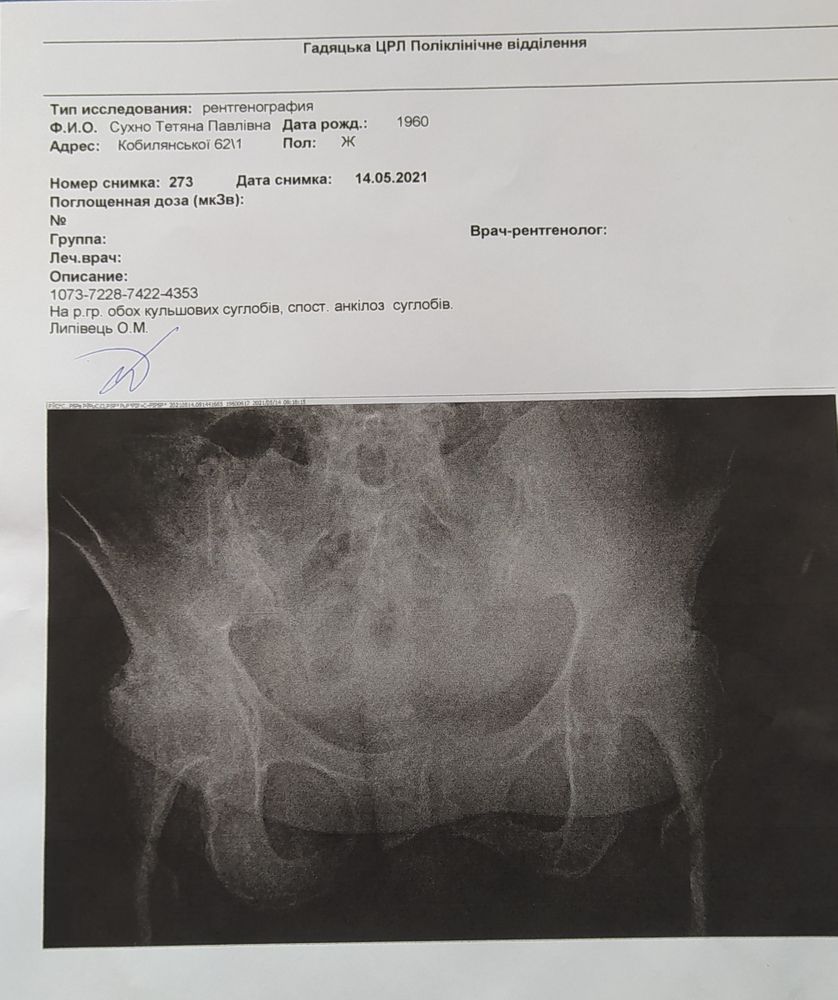

Опорно-двигательный аппаратКто проходил через такую операцию? Мама почти не передвигается, только с костылями по дому, сильные боли, постоянно на обезбаливающих.Протезировать нужно два сустава, коксартроз 4 степени. Очень страшно и дорого,собираю нужную сумму. В понедельник ложимся на госпитализацию, мама боится что не переживет. Мне тоже страшно. Плюс все усугубляктся диабетом. При повышенном сахвре плохо приживается протез.